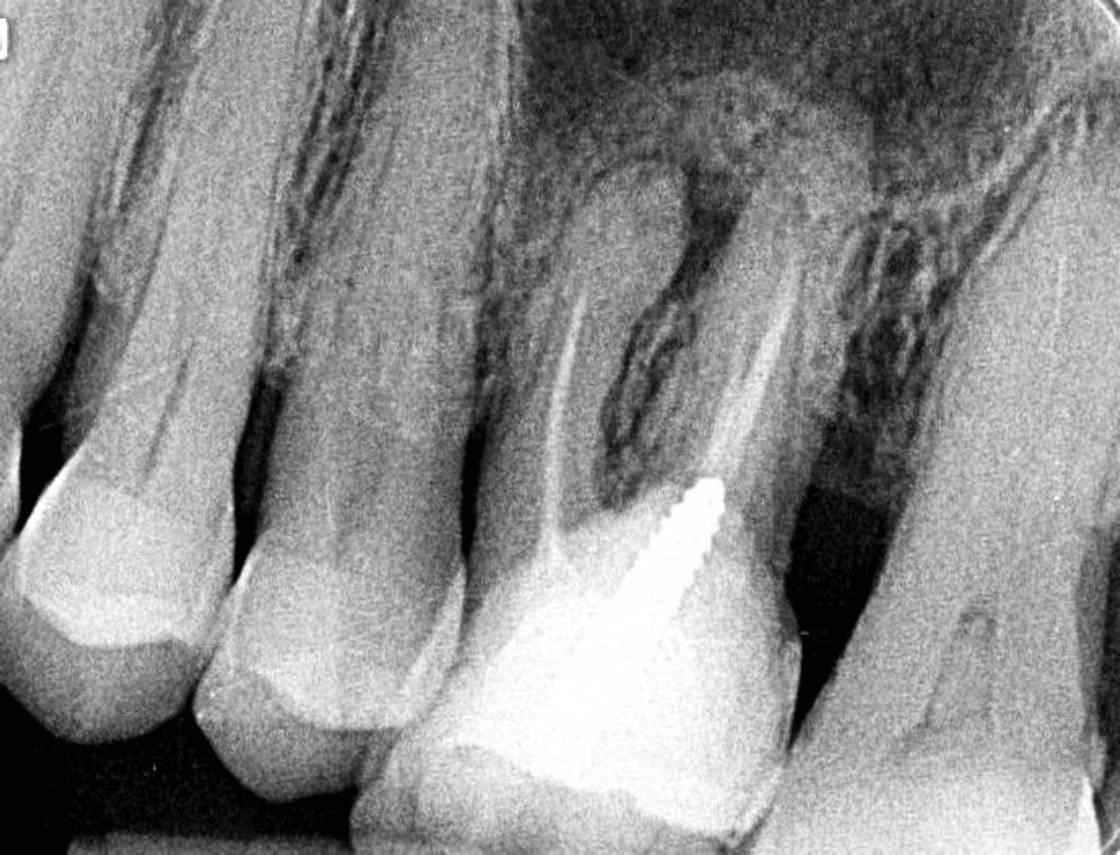

With the patient’s consent, X-rays were performed. Orthopanoramic images showed no macroscopic alteration of the bony structures, whereas an intraoral radiograph revealed a radiolucent apical lesion on tooth 2.6, suggesting a possible diagnosis of odontogenic abscess (Fig. 2). Therefore, a new antibiotic therapy (clindamycin 900 mg a day for 6 days) was prescribed, and an echography was scheduled for a more detailed evaluation of the swelling. The patient was re-evaluated three days later, showing no signs of improvement. The ultrasound showed a profound alteration in the intramuscular portion of the left cheek (buccal space), with a 3x2 cm central inhomogeneous portion with irregular and blurred edges. This central area was surrounded by a hyperechoic halo, suggesting a granulomatous reaction (Fig. 3). After further investigating the medical history and conducting an additional interview with the patient, it was found out that she had previously undergone a treatment with ozonized sunflower oil (Ozosan Gel, Bioactiva, Vicenza, Italy) used locally, after the use of anesthesia. Thus, the possibility of an off-label periapical injection of ozonized oil was considered. Only an injection administered coronal to the upper insertion of the buccinator muscle could explain the accumulation in the cheek.

Pre-operative periapical radiograph revealing a radiolucent apical lesion on tooth 2.6, suggesting a possible diagnosis of odontogenic abscess.